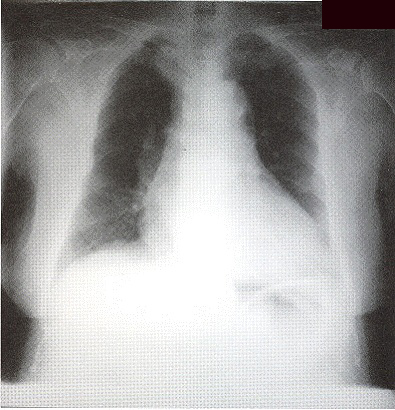

Complete blood picture showed mild neutrophilia. ESR was raised to 123mm/hr. She had mild renal impairment. Arterial blood gas on room air was nonnal on admission. Albumin/globulin ratio was reversed. Liver profile was normal. Sputum for culture grew oral flora and all smears for acid-fast bacilli were negative. CXR (Fig I) showed bilateral patchy opacity with nonnallung volume. No abnonnal mediastinal shadow was found. Old CXR of this patient was nonnal (Fig 2).

Figure 2